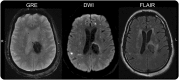

Figure 1. MRI

Left periventricular hemorrhage (gradient recalled echo [GRE], left panel) in a 45-year-old black man with hypertension. Middle panel (diffusion-weighted imaging [DWI]) shows multiple scattered ischemic lesions remote from the hematoma. Right panel (fluid-attenuated inversion recovery [FLAIR]) shows moderately severe white matter disease. The delta mean arterial pressure prior to the MRI was 106 mm Hg.